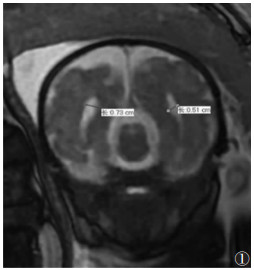

使用1.5 T Philips MRI B-TFE快速扫描技术进行扫描。扫描序列和参数:二维快速稳态进动序列和单次快速自旋回波序列,TR 3.5~5.0 ms,TE 1.5~1.8 ms,翻转角5°~60°,带宽125.00 Hz/像素,矩阵236×236或256×256,采集次数2次,层厚4~6 mm,间隔1 mm,FOV 36 cm×36 cm。胎儿头颅横断位及冠状位扫描须在出现完整胎儿形态的基础上再依据胎儿的矢状位重新定位扫描,须在上一个序列扫描完成的基础上进行,在侧脑室水平(脉络丛视野良好)测量[6]图 12)。

图 1 胎儿头颅MRI扫描的冠状面,测量侧脑室的直径